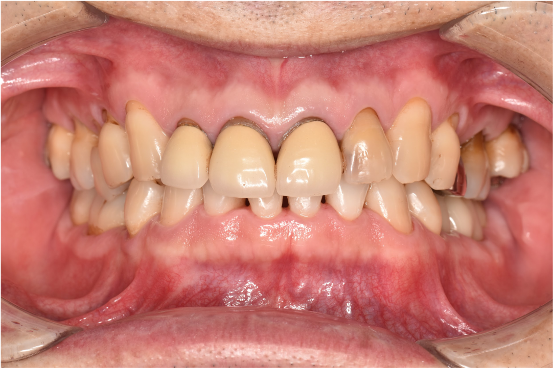

治療後

| 行ったご提案・治療内容 | 初診時に撮影したレントゲン、口腔内写真、歯周検査の結果を用いて、着色除去、歯周病治療の必要性をお伝えしました。 初診時は歯ブラシのお話しをさせていただき、セルフケアの方法について説明を行い、その後気にされてみえた着色除去、歯肉縁上歯石除去を行いましました。 歯肉の炎症がある程度落ち着いたところで、後日、再評価を行い歯周治療へ移行しました。 |

| 術後の経過・現在の様子 | 術後の経過は順調で、着色除去後、鏡でお口の中を確認をしていただいたところ、「とても綺麗になった!ご丁寧にありがとうございます」と仰っていただけました。 |